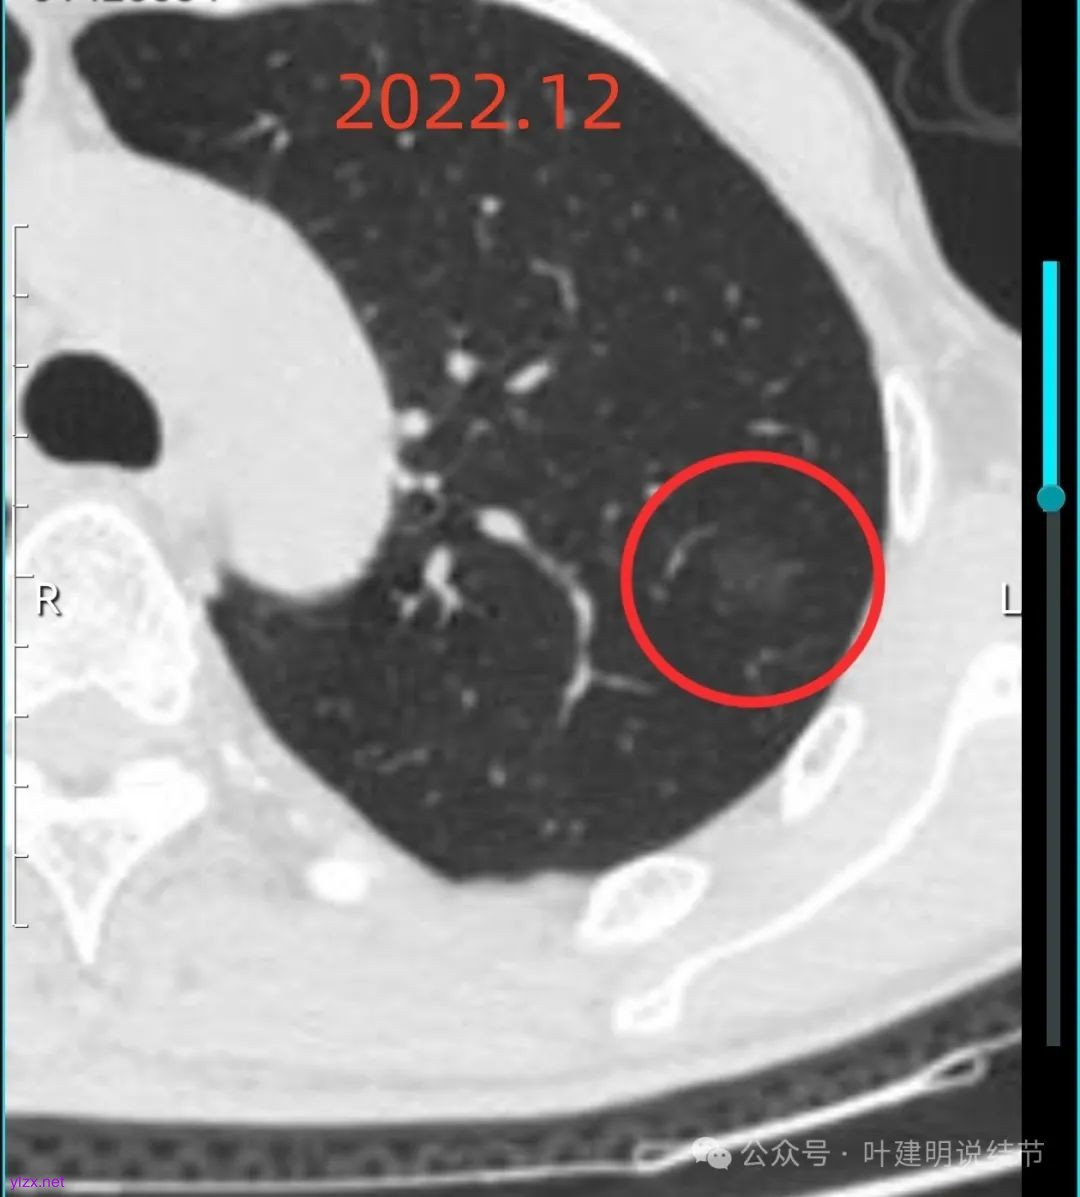

左上病灶血管进入了病灶且有异常增粗,边缘有淡的细毛刺的样子。

灶内血管明显,管壁略毛糙,有异常增粗,红色箭头处有点状高密度,边缘有毛刺征。

灶内出现了明显的实性成分,整体轮廓较清。

除了原血管进入外,另外角度也见到其他血管发出分支走向病灶,而且灶内密度不均,实性成分明显。

绿色的像是慢性炎,随访没有进展;红色的2022年12月开始是纯磨玻璃密度,但有小血管进入和整体轮廓较清,这种密度风险不高,但随访持续在的话,则要考虑肿瘤范畴,不典型增生或原位癌可能性大。再看2025年12月的,范围有所增大,磨玻璃部分密度仍很淡,但灶内出现实性成分,实性成分不太密实,稍显模糊。我觉得像微浸润性腺癌或原位癌伴肺泡塌陷可能性大。位置还好,病灶也不太小,若再增大进展切除范围更多些,我倾向单孔胸腔镜下局部楔形切了为妥。意见供参考!